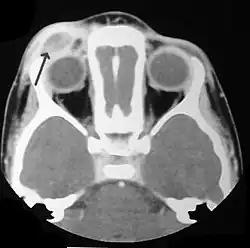

El diagnóstico se realiza por confirmación histológica a través de una biopsia tisular. La tinción de hematoxilina-eosina de la biopsia mostrará algunas características de las células de Langerhans como por ejemplo, gránulos plasmáticos rosados y margen celular distintivo. La presencia de gránulos de Birbeck en la microscopía electrónica y las características inmunohistoquímicas como por ejemplo la positividad para CD1, resultan pruebas más específicas. Algunos exámenes de laboratorio de rutina como el hemograma, perfil hepático, y otras pruebas sirven para orientar el diagnóstico (principalmente para descartar otras posibles causas). Los exámenes imagenológicos mostrarán lesiones osteolíticas y daño pulmonar. Esto último se puede evidenciar en la radiografía de tórax al mostrar lesiones micronodulares e infiltrados pulmonares en las zonas bajas y medias. La resonancia nuclear magnética o la tomografía axial computarizada puede mostrar infiltración a nivel de la silla turca. La medición del eje endocrino y la biopsia de la médula ósea también pueden resultar útiles para el diagnóstico.